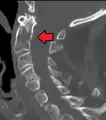

A fracture of the base of the dens as seen on plain X-ray

A fracture of the base of the dens as seen on CT